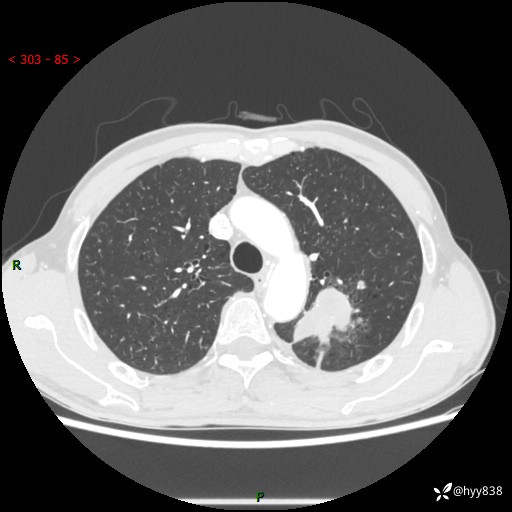

老年男性,咳嗽咳痰伴痰中带血4月。沿支气管铸形生长的不多---结果公布~

现病史:患者余4月前发现咳嗽咳痰伴痰中带血,无胸闷、胸痛、头晕、恶心、呕吐等不适,2天前因体检发现肺部结节遂于当地市第一人民医院行胸部CT薄层平扫+三维重建示:1.左肺上叶尖后段占位性病变考虑肿瘤性病变伴阻塞性肺炎,右肺上叶后段磨玻璃结节。2.肝内多发囊性灶、左肾结石。现患者为求进一步治疗,于我院门诊就诊,门诊以“肺结节”收入院。 自患病以来,精神、饮食、睡眠尚可,大小便正常,体力体重无明显减轻。

胸部CT增强扫描(外院平扫)